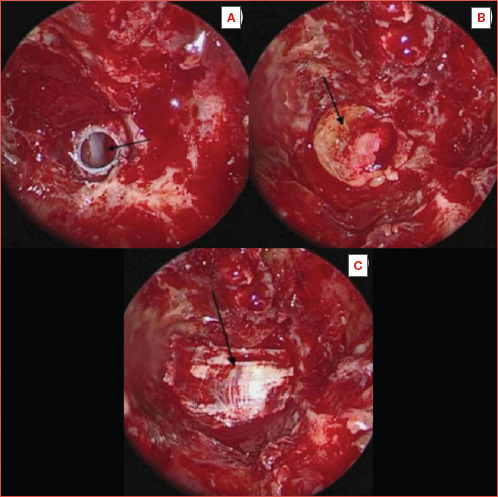

Results: We present 5 cases of retroclival EP (4 males, 1 female; age range, 34-81 years) presenting in our department over the last 6 years. Four patients presented with CSF leak; 3 also had a history of bacterial meningitis, while one was diagnosed with meningitis on presentation. One patient was and remains asymptomatic 28 months later with the lesion being an incidental finding. The EP was treated in all 4 symptomatic patients with removal of the lesion and reconstruction of the defect with an endoscopic endonasal transclival approach (EETTA). All 4 patients remain free of symptoms while the lesion has not recurred for 81, 72, 52, and 22 months, respectively.

Conclusions: A review of the literature depicts that there is a shift from transcranial approaches to the EETTA for treating retroclival EP. The present case series highlights that EETTA facilitates the complete excision of EP lesions, as well the reconstruction of the resulting defects, with minimal morbidity and hospitalisation.